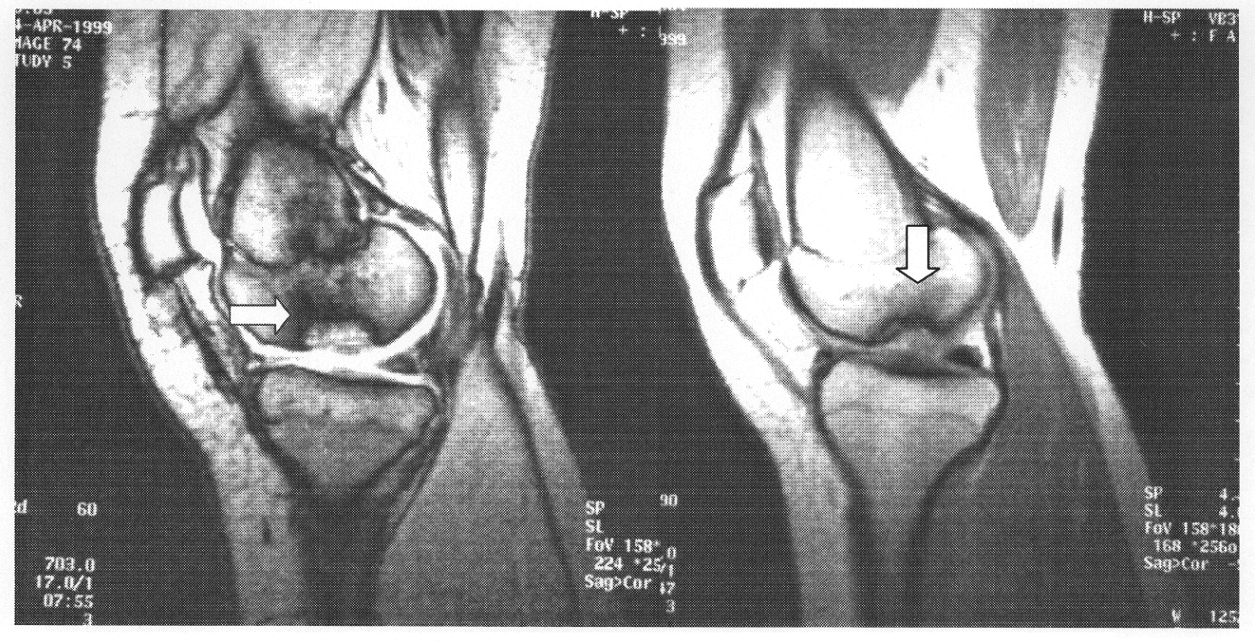

Даже если врач заметил изменения в суставе на рентгеновском снимке, он направит пациента на магнитно-резонансную томографию (МРТ). Этот метод диагностики наиболее информативен при болезни Кенига. С его помощью можно определить:

- местоположение очага поражения;

- размеры поврежденной области;

- состояние хрящевой ткани и субхондрального слоя кости;

- наличие отека в костном мозге;

- наличие свободно движущегося фрагмента в суставной полости.